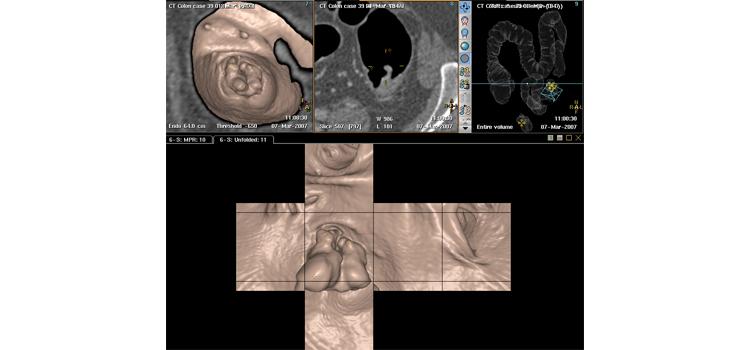

Computed tomography colonography (CTC), also known as virtual colonoscopy, offers a noninvasive alternative to ...